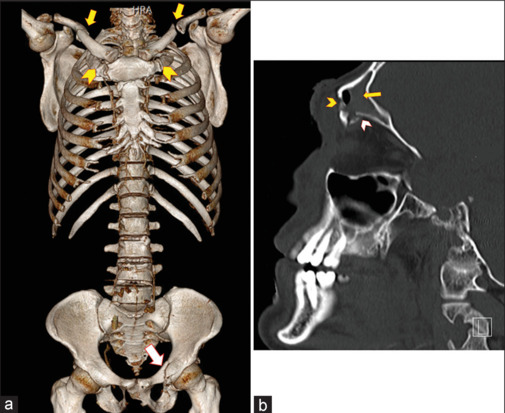

Introduction: Unilateral fracture of the first rib frequently led to severe complications such as brachial plexus or major vascular injury. Bilateral first rib fracture (BFRF) is very rare. We aimed to study the incidence, mechanism of injury, management, and outcome of BFRF in blunt trauma patients in a community-based hospital.

Results: During the study period, 4779 patients with blunt trauma were included in the trauma registry and 12 (0.25%) patients had BFRF. The mean age of standard deviation (SD) was 29 (8.3) years. Seven (58.3%) patients were involved in road traffic collisions and 5 (41.7%) patients fell from more than 3 m height. The most commonly associated thoracic injury was lung contusions in 8 (66.7%) patients. The median (range) Glasgow Coma Score on admission was 15 (14-15) and Injury Severity Score (SD) was 19 (10.5). Length of hospital stay mean (SD) was 6.8 (6.4) days. No patients died in the study.

Conclusions: BFRF is a rare entity in blunt trauma patients caused by high-energy trauma. Major vascular or brachial plexus injuries in patients with BFRF are much less than those reported in the medical literature on unilateral first rib fractures. Associated injuries are the main cause of trauma-related morbidity rather than the direct effect of BFRF.